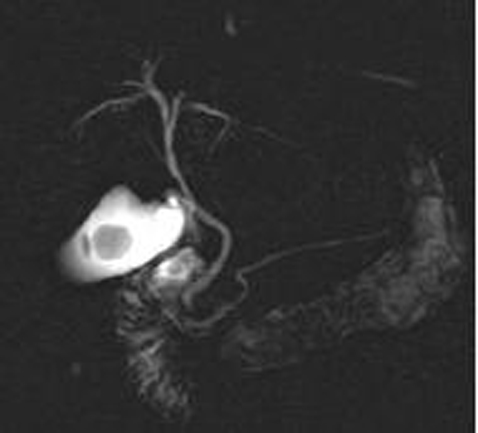

Image IRM et

cholangio -IRM ( MRCP ) : Image de calcul

de la vesicule biliaire est lacule a hyposignal dans

la vesicule remplie de liquide hyperintense

Image radiologique

cholangio -IRM : Image de la lithiase est lacule

hypointense a interieure la vesicule remplie de bile

hyperintense . Voie biliaire pricipale , voie

intrahepatique et canal de Wirsung en voyait

complete et nette |